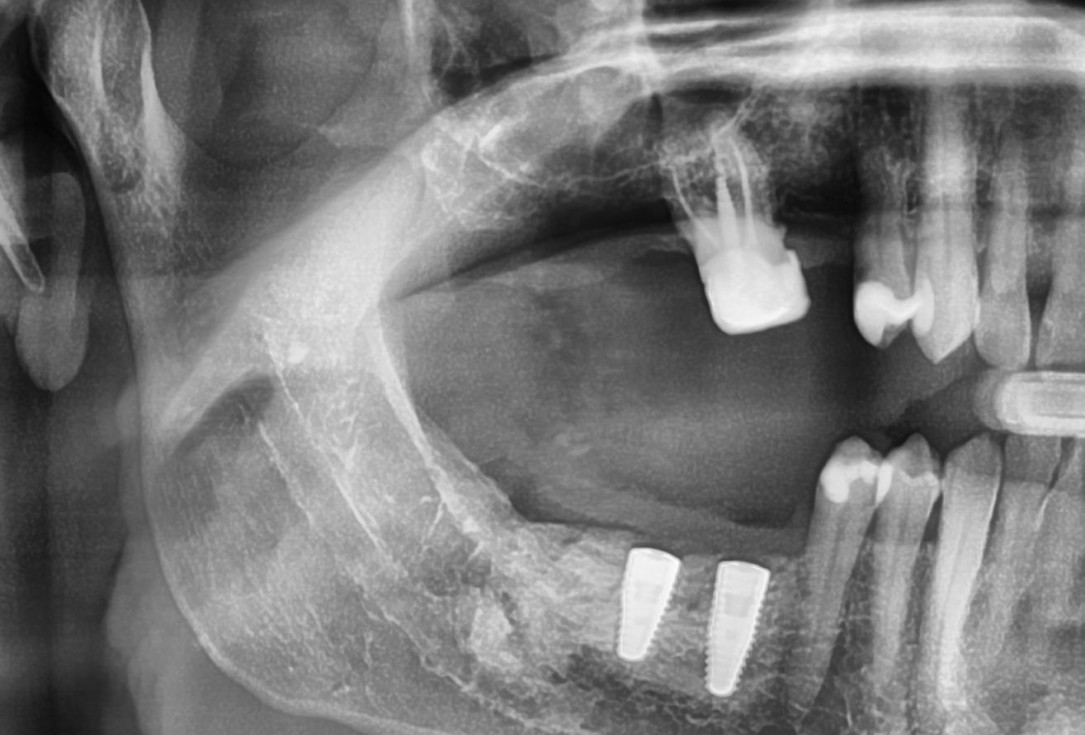

11/28 - X-ray scan after augmentationThree-dimensional augmentation with maxgraft® cortico - Dr. R. Würdinger

Pre-operative radiographic view.

X-ray control showing initial situation